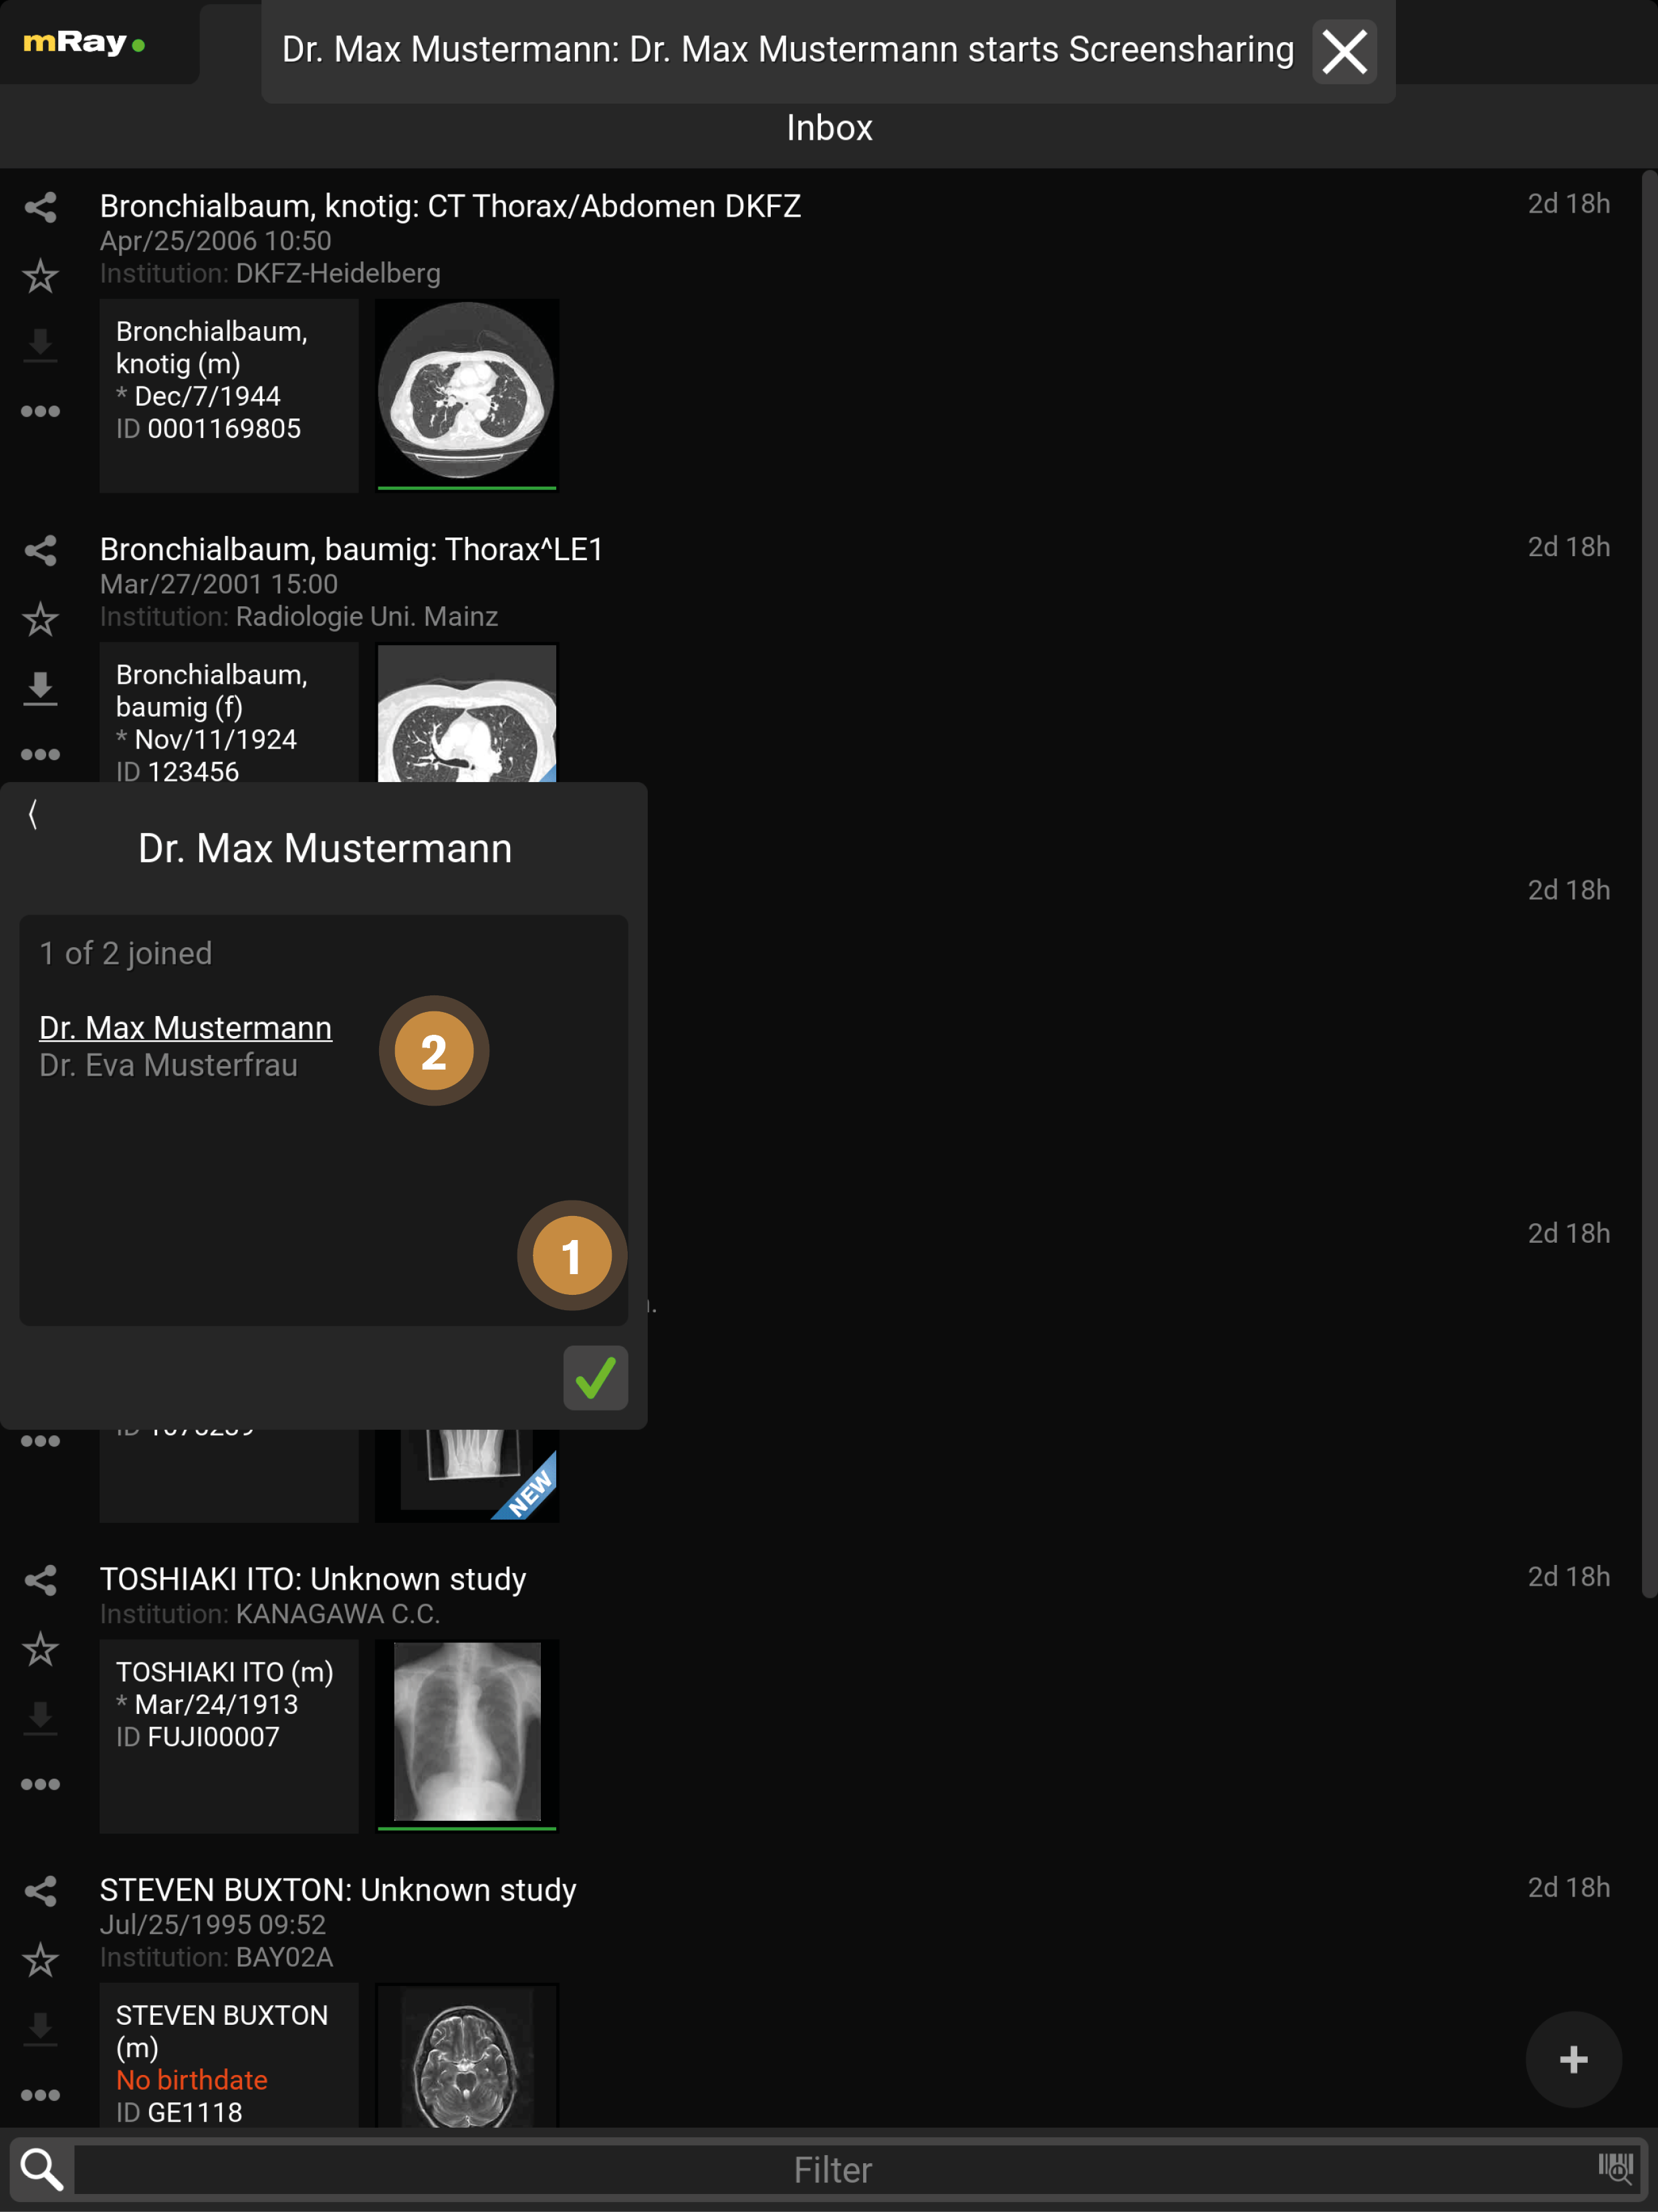

9.1. Inbox

The (Inbox) will be opened after logging in. With this you can browse and select the wanted DICOM files, which are enabled for you through the server. Thus you can see all files on the mRay server on which you have access rights.

By clicking the mRay logo you can open the main menu (see Main menu).

A green dot shows, if you are connected to the server. In case of a red dot you can work with the local saved files, but of course you can’t receive new files.

Switch to the Inbox or return to the beginning of the list if it is the active tab.

Switch to the Messaging menu (only if this function has been activated in your system).

Switch to the Search dialog. Here you can search the whole mRay database or query a PACS (if configured).

Switch to Favorites: It is possible to mark your favorites with the star symbol (Item 9). Favorites are working as a kind of bookmark and they will be deleted last by the automatically storage management of the application (which means your favorites will only be deleted if it is necessary due to your Settings to the data retention or due to low space on your device).

Switch to the Photo documentation

Click here to return to the viewer with the previously opened images.

Here you are able to quickly and easily share

, mark as favorite  or export

Further actions on the whole study can be performed with the Context menu

Further actions on the whole study can be performed with the Context menu  .

Shows information or rather missing information and meta data from a patient.

Shows an overview of the contained series in a study. By clicking a study you will get to the series selection (see Series selection). The green marker under any thumbnail indicates that the image data is stored locally and offline available.

The time will appear as soon as the data arrived in the mRay (by sending from a PACS and searching in the mRay database). mRay can be configured to automatically delete data after 'X' hours (default: after 8 hours).

Here enables selecting multiple studies for sharing.

Here you can filter your inbox by text entry. Please note: By filtering you don’t start a PACS query! See item 3 Search for PACS queries. Please also mind the notes to special characters in the 'known issues'.*

Take a photo: see Photo documentation section for further explanations

File-Upload: Upload your own DICOM data to the server. Only available if the server supports it.